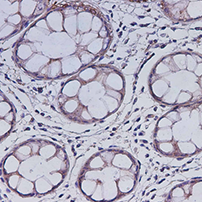

- 货号:E-AB-13771

- 宿主:Rabbit

- 反应性:Human;Mouse;Rat

- 应用性:WB;IHC

- 货号:E-AB-13844

- 宿主:Rabbit

- 反应性:Human;Rat

- 应用性:WB;IHC

- 货号:E-AB-13959

- 宿主:Rabbit

- 反应性:Human;Mouse;Rat

- 应用性:WB;IHC

- 货号:E-AB-14052

- 宿主:Rabbit

- 反应性:Human;Mouse;Rat

- 应用性:IHC

- 货号:E-AB-14100

- 宿主:Rabbit

- 反应性:Human;Mouse;Rat

- 应用性:IHC